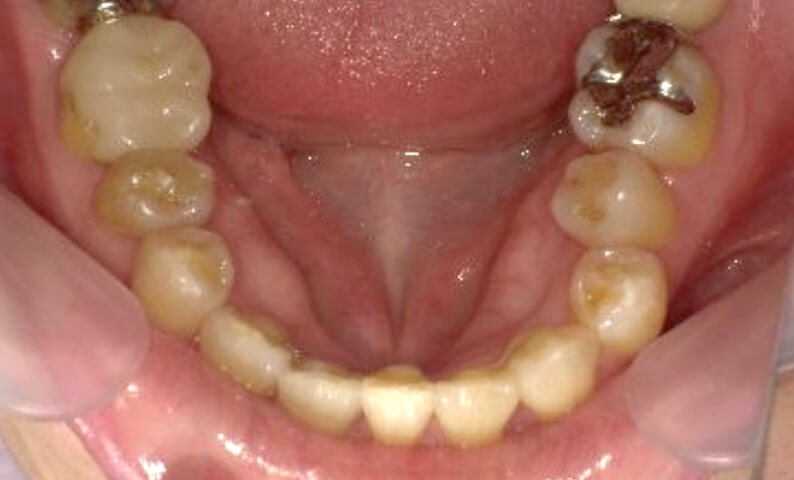

症例_001 下顎だけの部分矯正

治療期間:8ヶ月金額:21万円+税女性前歯のガタガタ下の前歯だけ

| Before | After |

|---|---|

|